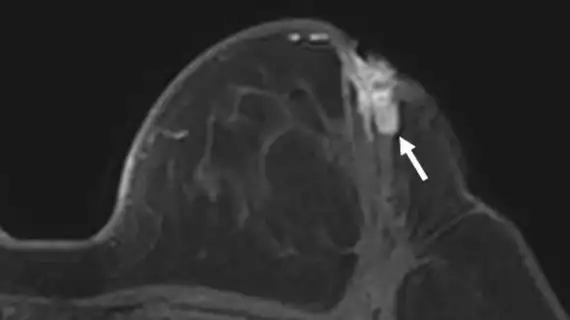

Calcific Subcoracoid Bursitis